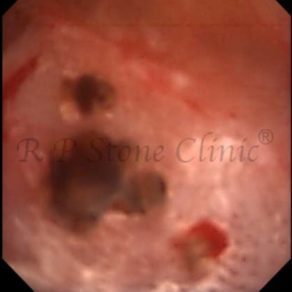

Kidney stone is a solid mass of CRYSTALS. It is the process of crystallization which initiates the formation of kidney stones. This happens in nephrons or units of kidney. Once a small crystal is formed, it can both grow & unite with other crystals leading to the formation of small concretion which eventually forms a stone. Once these large crystals detach from the collecting ducts, the process of stone formation starts in the renal collecting system. A recurrent kidney stone former is advised to know a little bit about something known as Randall’s plaque. Alexander Randall discovered plaques on the renal papillae eight decades back based on examination of 1154 pairs of autopsied Kidneys. He described these renal papillary lesions as cream colored or milk patch areas composed of calcium phosphate & calcium carbonate. These plaques could act as NIDUS for formation of KIDNEY STONE. Calcium Oxalate stone can form on this nidus & then detaches from this plaque to become a free floating stone in the collecting system of kidney

These images are taken as snap shots from the video recording of RIRS Surgery done at our hospital. These are Randall’s Plaques seen with Digital FLEX XC & Digital FLEX XC S. The cream or whitish patches are seen on the tips of RENAL PAPILLAE as seen in images below.